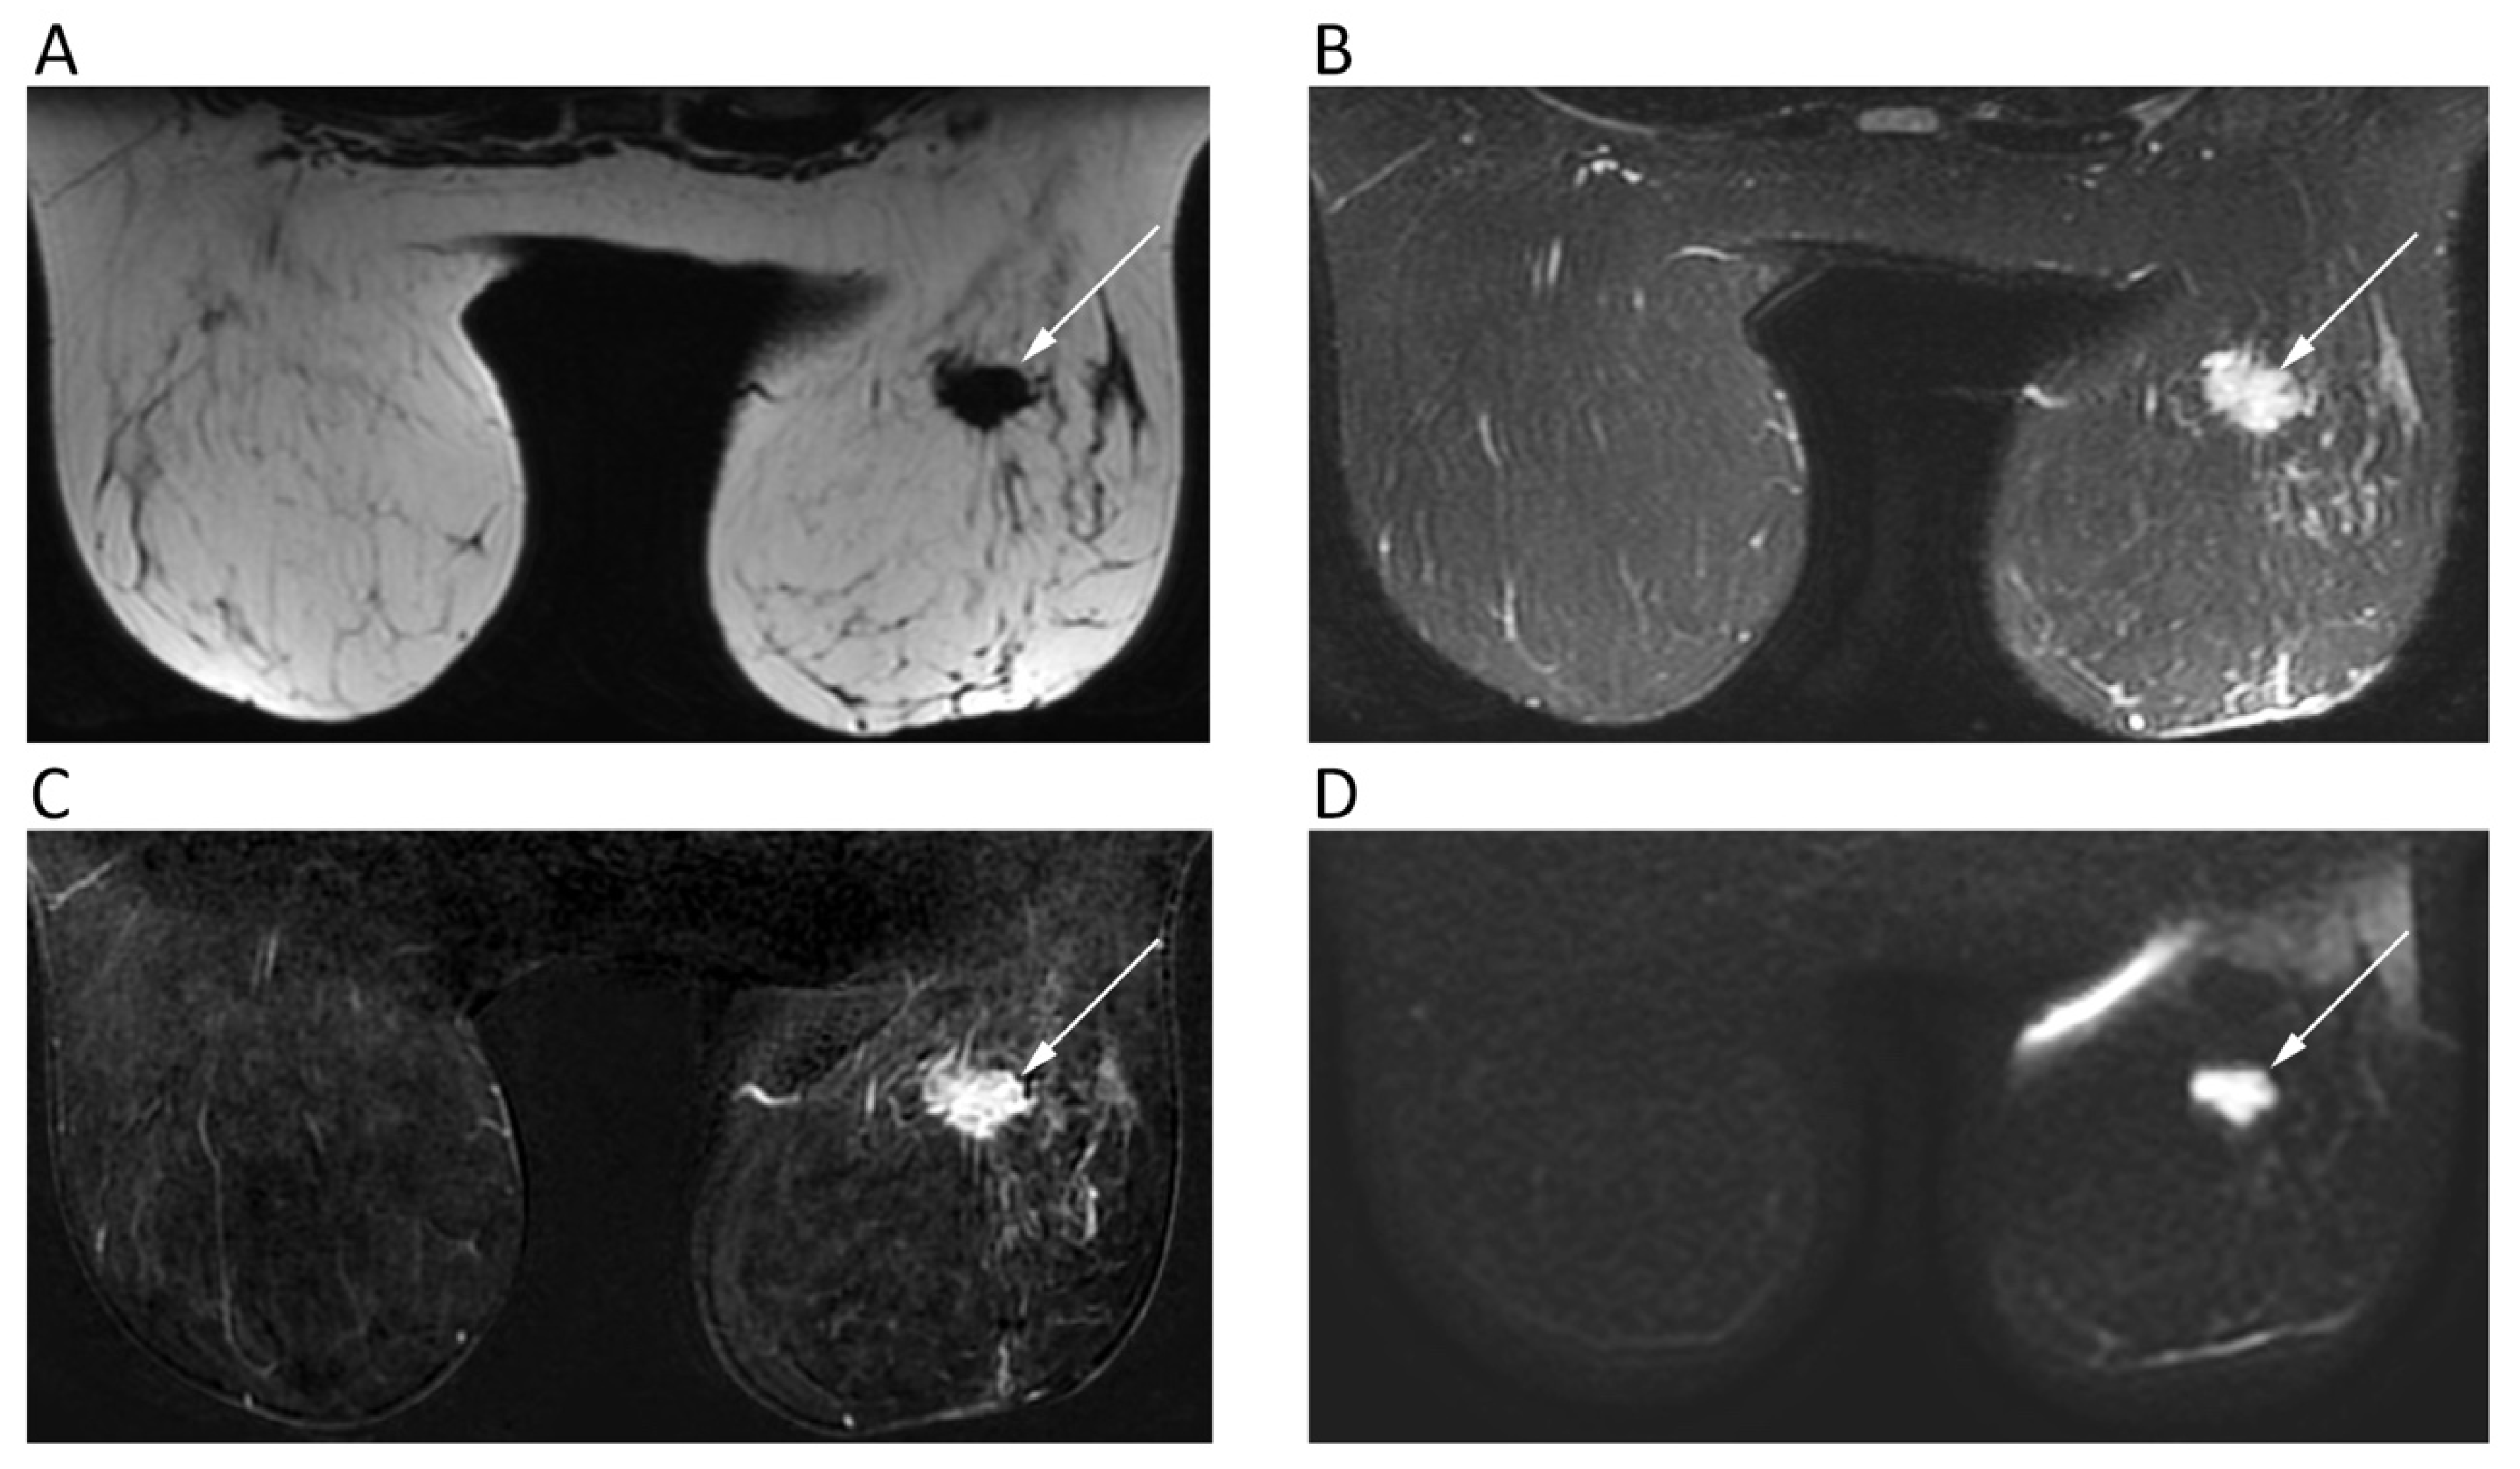

Dynamic contrast enhanced (DCE)-MRI has a crucial role in clinical practice of evaluating suspicious breast lesions [23]. However, as an additional tool, DWI has been tested for several purposes, mainly being used with two b-values (b = 0, b = 800). DWI has been investigated as a stand-alone approach for breast cancer detection, although the diagnostic performance of DCE-MRI still exceeds that of DWI, with the latter presenting 84%–86% sensitivity and 76%–79% specificity [23]. Nevertheless, the added value of DWI is proven by the higher accuracy of combined DCE/DWI-MRI (94%) than that of DCE-MRI alone (85%) for breast cancer detection [24]. Further, although breast malignancies present a restricted pattern of diffusion (Figure 4), DWI has a limited role in distinguishing benign from malignant breast lesions if compared to DCE-MRI. Moreover, invasive tumors tend to present lower ADC than carcinoma in situ [25]. In this setting, a high b-value (b = 900/1000) improves the discrimination of breast lesions from the neighboring soft tissue [26], although the best choice of b-values to be used in breast DWI is still debated. In fact, higher b values increase the specificity of DWI sequence at cost of decreased signal-to-noise ratio, thereby leading most authors to prefer a b = 800 image [27].

Figure 4.

Breast MRI of a 42-year-old female patient with right breast carcinoma. Axial IDEAL fat only (A) and IDEAL water only (B) images show a right breast carcinoma (arrows) with strong enhancement on post-contrast T1w image (C) and high signal intensity on b = 900 DWI image (D).